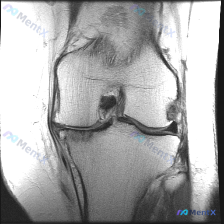

刚看到一张有意思的膝关节MRI读片病例,整理出来分享下思路。 病例影像资料 提供的是膝关节MRI-T1加权序列冠状位图像,分析可见: 1. 骨骼结构:股骨远端、胫骨近端皮质连续,无明显骨折或骨质破坏;T1序列骨髓信号为弥漫中等信号,无明显异常低/高信号 2. 半月板:内、外侧半月板形态信号均正常,内...